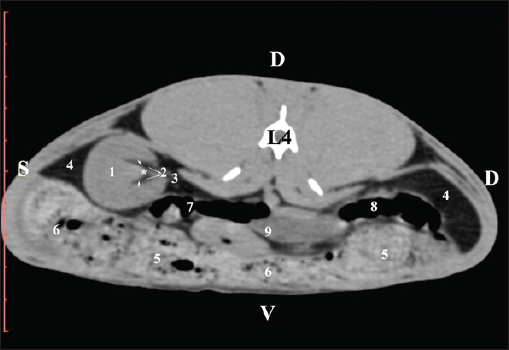

Fig. 9. Pre-contrast computed tomography (CT) anatomical scan of the regio-abdominis media at the caudal L3 edge level. (1) Ren dexter; (2) adipose collections; (3) cecum; (4) colon ascendens; (5) jejunum; (6) pars ascendens of the duodenum; (7) colon descendens. The pre-contrast anatomical scan at the L4 level provided data about the location of the renal pelvis within the renal sinus. The initial part of the pelvis renalis appeared as a distinct funnel-shaped hypoattenuated soft tissue, whose central part was widened and formed the recessus renalis. The transition of the narrowed end of the renal pelvis into the hypoattenuated left ureter was without a sharp boundary. The left kidney was in contact with the cecum, colon ascendens, and colon transversum ventrally. Crista renalis was observed as a hypoattenuated linear soft tissue finding (Figs. 10 and 11).

Fig. 10. Pre-contrast computed tomography (CT) anatomical scan of the regio-abdominis media at the cranial L4 edge level. (1) Ren sinister; (2) pelvis renalis and crista renalis; (3) ureter; (4) cecum; (5) colon ascendens; (6) colon transversum; (7) colon descendens; (8) adipose collections.

Fig. 11. Pre-contrast computed tomography (CT) anatomical scan of the regio-abdominis media at the caudal L4 edge level. (1) Ren sinister; (2) pelvis renalis; (3) ureter; (4) adipose collections; (5) cecum; (6) colon ascendens; (7) colon transversum; (8) colon descendens; (9) mesenterium; (white arrows) recessus renalis; (*) crista renalis. The L5 scan revealed the caudal end of the left kidney. It was adjacent to some small intestinal segments, including the duodenal pars ascendens, ileum, cecum, and colon ascendens (Figs. 12 and 13).